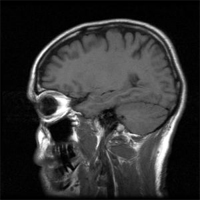

Gehirnscan: Hoher Blutdruck führt zu Schädigungen und Verkleinerungen der Gehirnmasse (Foto: stock.xchng Image ID: 370098)

In der Untersuchung der University of California wurde bei 579 Personen im Durchschnittsalter von 39,2 Jahren das Gehirn gescannt. Dabei entdeckten die Ärzte, dass Menschen im Alter von 30 Jahren mit erhöhtem Blutdruck ein Gehirnprofil aufwiesen wie 40-Jährige, die einen ganz normalen Blutdruck hatten. Die Gehirne der Bluthochdruck-Patienten zeigten eine Verringerung des Gehirnvolumens sowie Schäden der Nerven und Gefäße. Diese Art von Schäden werden von Neurologen als typische Merkmale einer demenziellen Erkrankung bezeichnet. Was dazu führt, dass Bluthochdruck das Gehirn altern lassen kann, erklären Experten so: Der hohe Blutdruck versteift oder verhärtet die Gefäße. Und diese Gefäßveränderungen behindern die Blut- und Sauerstoffzufuhr zum Gehirn.